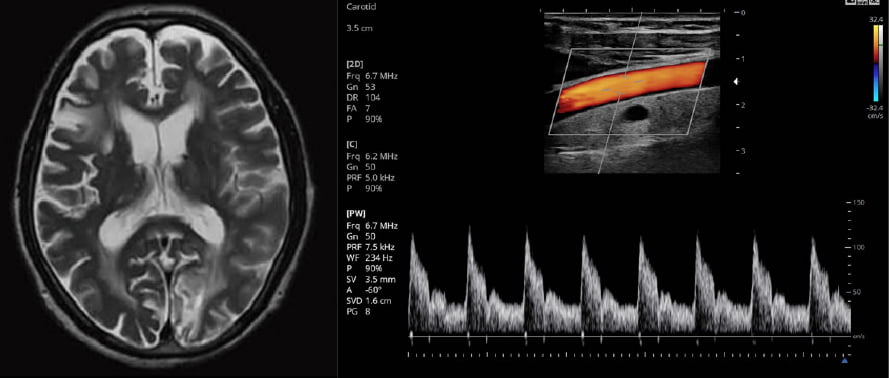

先端医療機器(MRI・超音波エコー)の

導入で精密検査に対応

当院では1.5テスラMRIを導入しております。これにより脳や脊椎,四肢,子宮・卵巣・前立腺といった骨盤内の病変検出能力で本格的な精密診断を可能にしています。また、超音波エコーは血管内の異常を発見することが可能です。これらの機材を導入し、皆様へは妥協のない真摯な姿勢で診療に務めます。

MRIや超音波エコーによる診断は

脳の重大事態の早期発見に繋がります

脳梗塞、クモ膜下出血等の症状を事前に予見することで、カラダの危険を知ることができます。頭痛・めまい・物忘れ・神経系のしびれ等の原因が特定しづらい症状がある方はお早めに診察を受けることをオススメいたします。